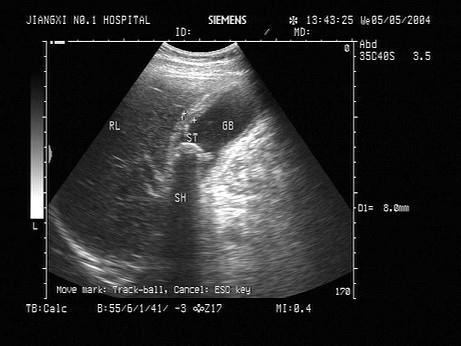

患者右上腹疼痛1周,厌油食,超声见胆囊内强回声,可移动,如图所示,考虑为?(?)A.胆汁淤积B.胆囊癌C.胆囊息肉D.胆囊结石E.胆囊蛔虫

问题 患者右上腹疼痛1周,厌油食,超声见胆囊内强回声,可移动,如图所示,考虑为?(?)

选项 A.胆汁淤积 B.胆囊癌 C.胆囊息肉 D.胆囊结石 E.胆囊蛔虫

答案 D